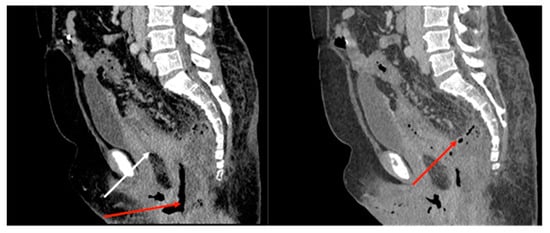

2.1. Case Report